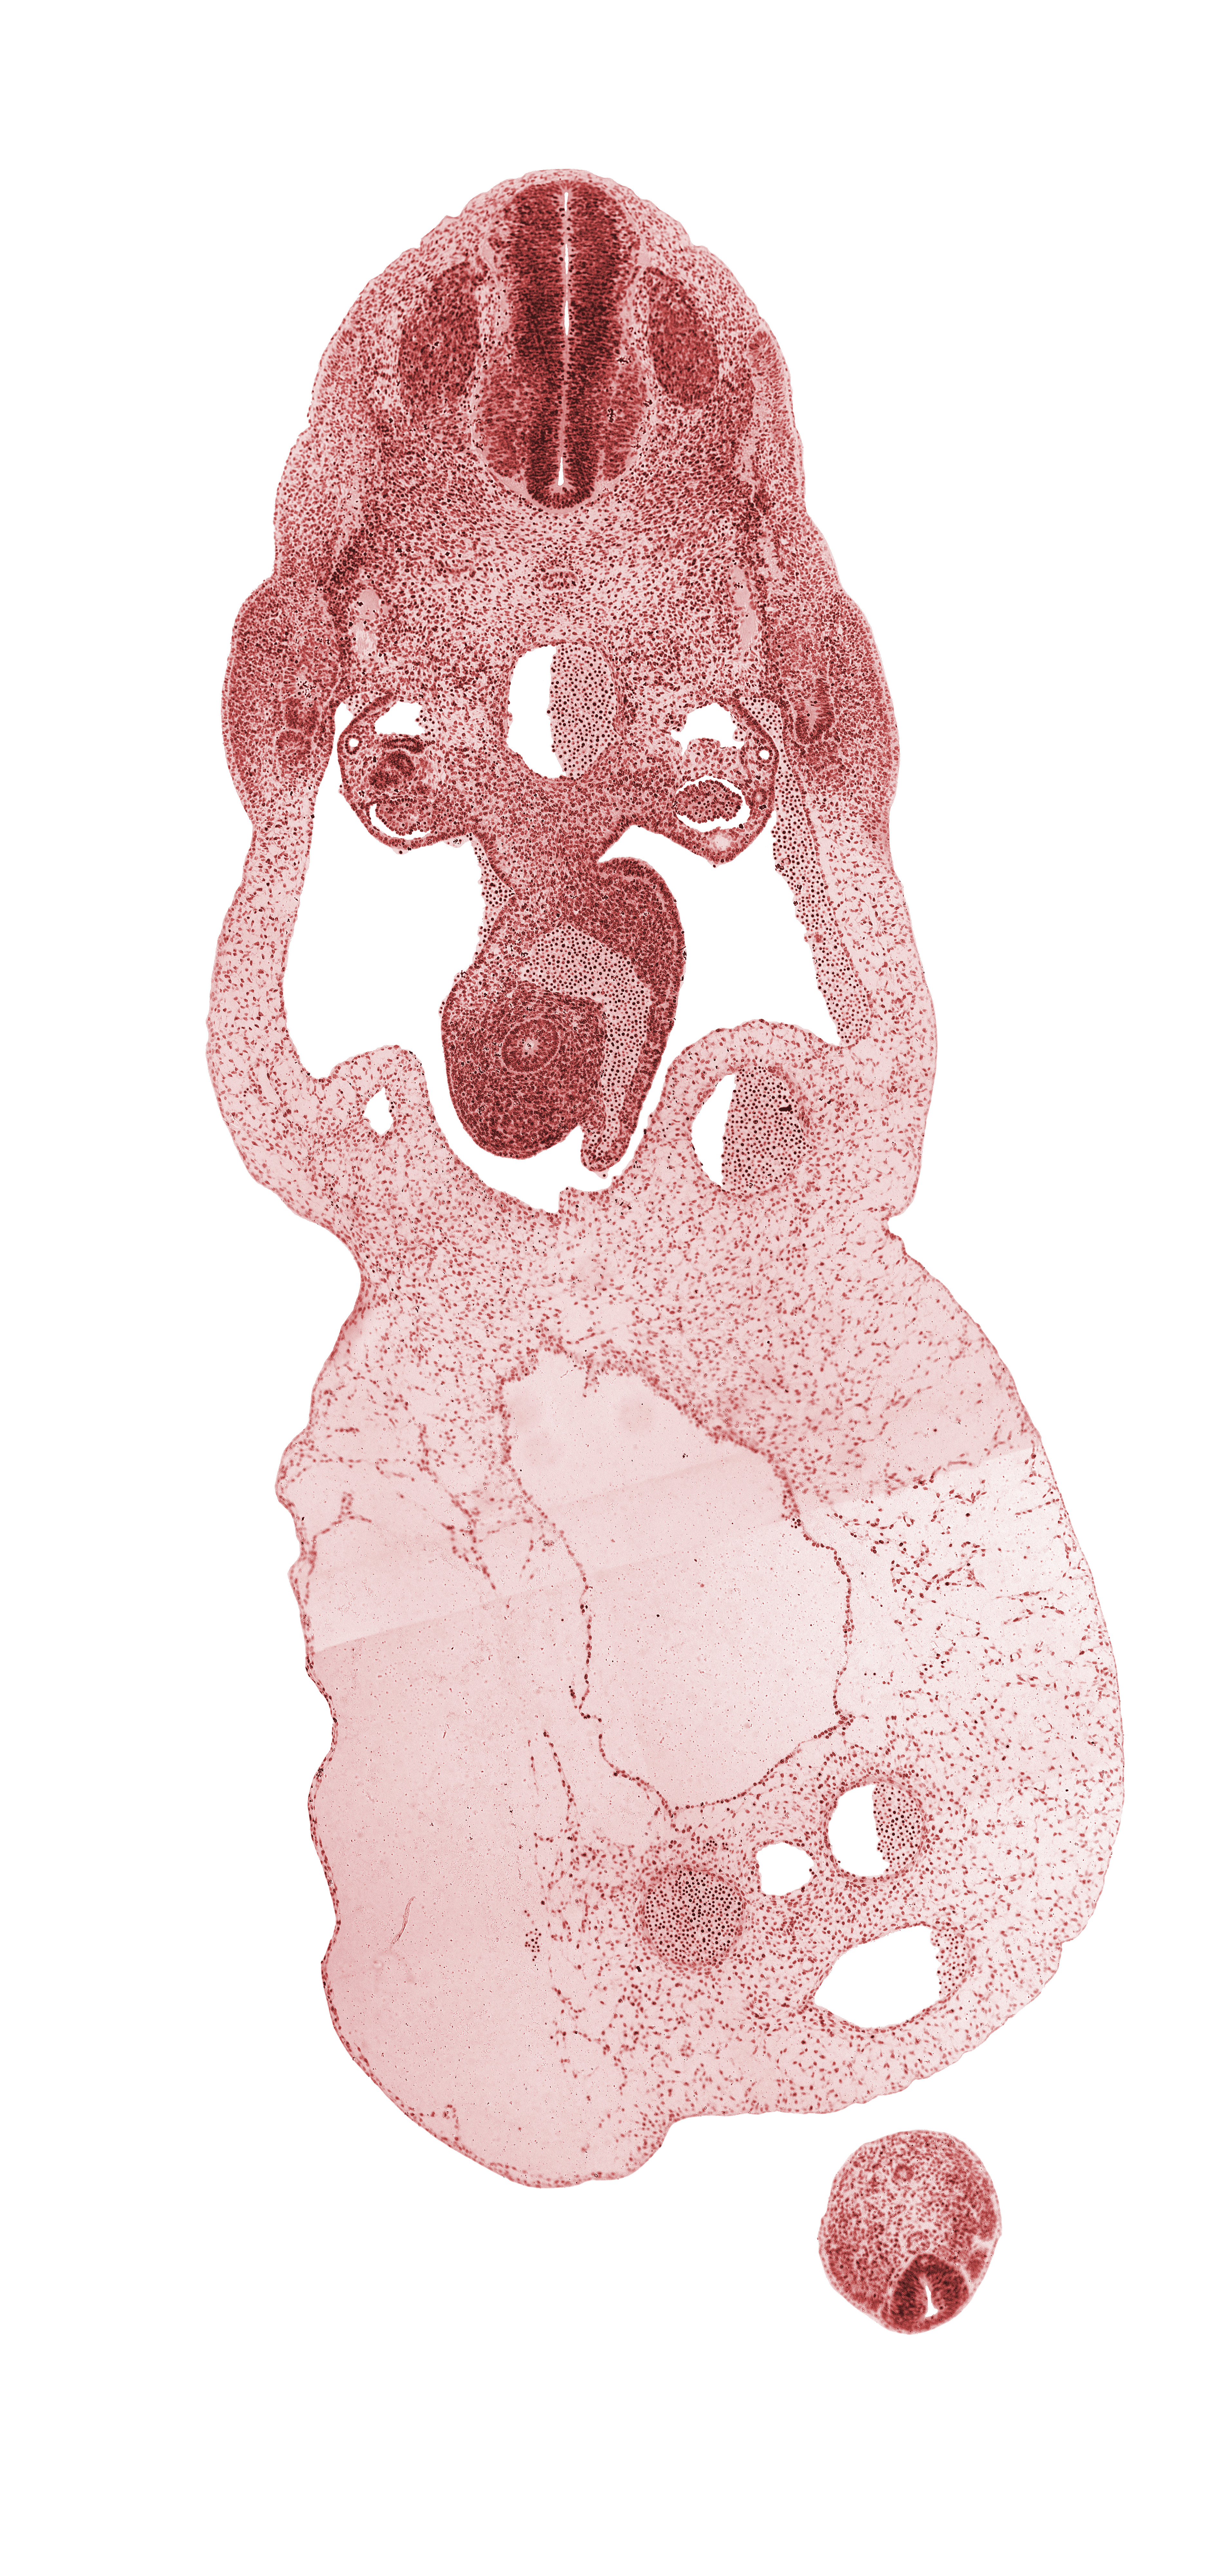

Carnegie Embryo #6502 | Location: 29-01-05

Keywords: Co-1 spinal ganglion, T-1 spinal ganglion, allantois, amnion on surface of umbilical cord, aorta, common umbilical vein, dermatomyotome, gonadal ridge, involuting right umbilical vein, left umbilical artery, left umbilical vein, mammary crest, mesonephric artery, mesonephric duct, midgut, myotome, neural canal, neural tube, notochord, omphalomesenteric (superior mesenteric) vein, peritoneal cavity, post anal gut, right umbilical artery, sclerotome, umbilical coelom, umbilical cord

Source: The Virtual Human Embryo.